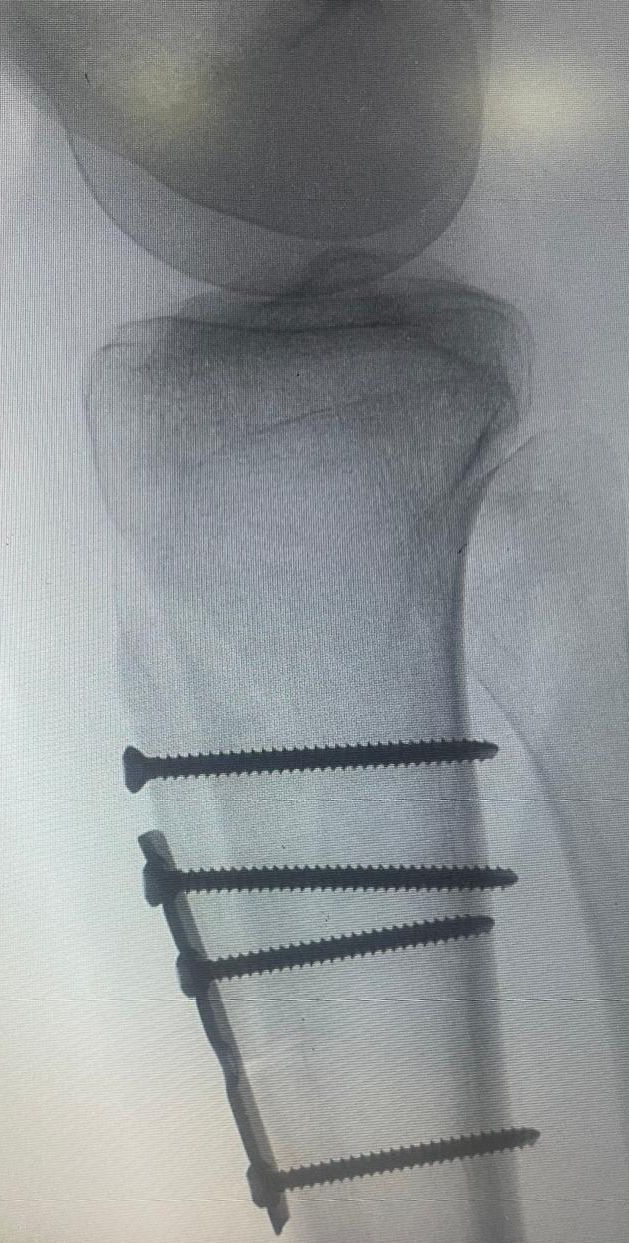

وتفصيلا قال الدكتور فهد الحليبي، استشاري جراحة العظام والإصابات الرياضية المعقدة ، ان المريضة حضرت لمجمع الدمام الطبي وهي تعاني من خلع متكرر في عظمة الرضفة بالركبة لعدة سنوات بالاضافة الى اختلال ديناميكية اوتار الركبة . حيث تقرر اجراء عملية قص جذر وتر عظمة الرضفة وتغيير مسارها وتثبيتها جراحياً، إلى جانب إجراء تثبيت جانبي لنفس العظمة باستخدام وتر العضلة الخلفية بتقنية المنظار الجراحي.وتتمتع المريضة بصحة جيدة بعد توفيق الله وتتابع التأهيل بمركز العلاج الطبيعي بالمجمع للوصول الى افضل النتائج .

وأكد ” الحليبي ” أن هذه الجراحة تُعد من العمليات النادرة في مجال جراحة العظام، حيث تتطلب خبرة ومهارة عاليتين، موضحاً أن مثل هذه الحالات كانت تُحول سابقاً إلى مراكز طبية خارج المنطقة ، مسلطا الضوء على التطور الكبير الذي حققه مجمع الدمام الطبي في مجال جراحة العظام. و دليلاً على التقدم الملحوظ الذي احرزه في علاج الحالات النادرة والمعقدة، وذلك بالاعتماد على أحدث التقنيات الطبية وتوفير فرق طبية مؤهلة للتعامل مع أدق العمليات الجراحية، مما يُسهم في الارتقاء بمستوى الخدمات الصحية المقدمة للاهالي في المنطقة الشرقية